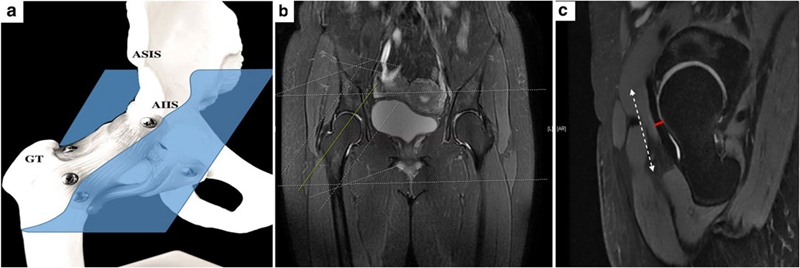

‌‌‌‌前关节囊除了进行X线指标的测量之外,我们尤其关注了厚度,测量方法选择在斜矢状位上,在整个前关节囊的‌‌中段进行了厚度的测量。见图9C中红色线段部位。

术前磁共振测量的案例